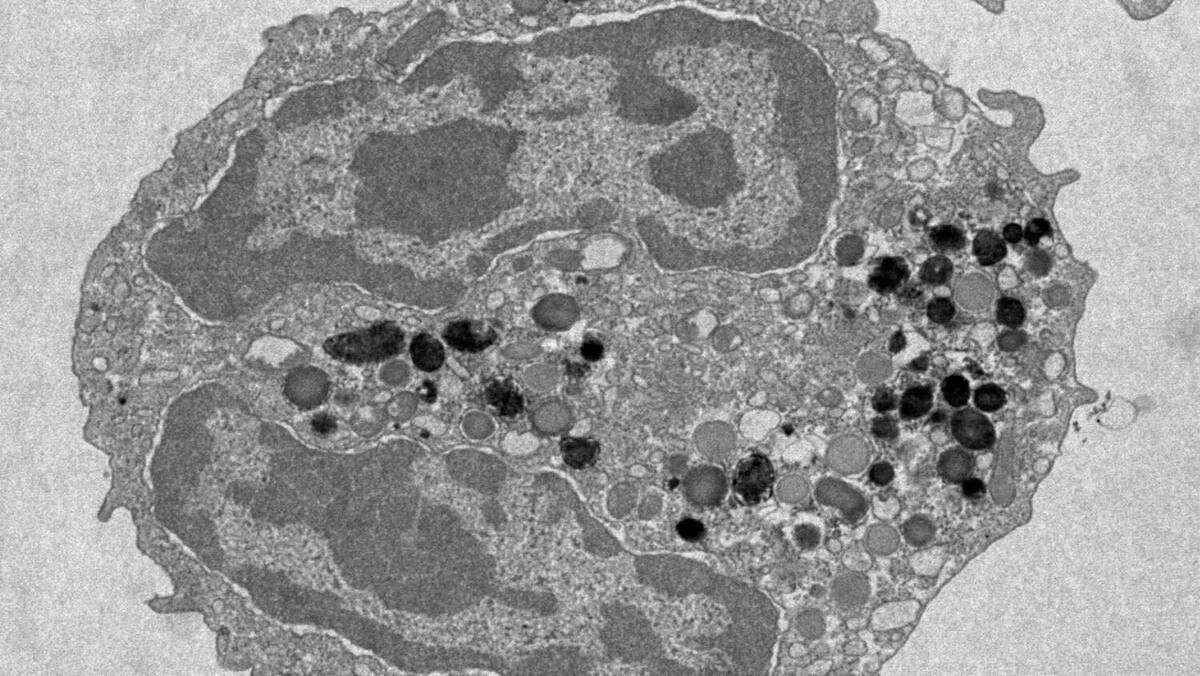

Изображение клетки крови под электронным микроскопом. Автор: Гектор Уэрга Энкабо. Источник: институт Фрэнсиса Крика